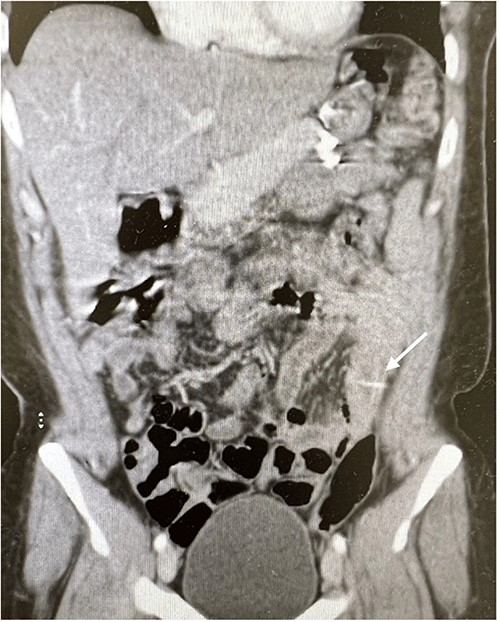

The abdominal exam showed severe tenderness in LLQ + rebound tenderness. The white blood cell count was 9000/mm3. Contrast-enhanced CT of the abdomen (Figs 1 and 2) showed a transversely oriented linear hyperdense FB structure seen within the ilea loops in the LLQ measuring ~2 mm in thickness and 18 mm in length traversing the bowel wall, which demonstrates localized mural wall edema with minimal surrounding fatty haziness; however, there was no adjacent extra-luminal air or localized collections, and right adnexal cyst.

Coronal views of contrast-enhanced CT abdomen showed: a transversely oriented linear hyperdense FB (arrow) structure seen within the ilea loops in the lower quadrant.